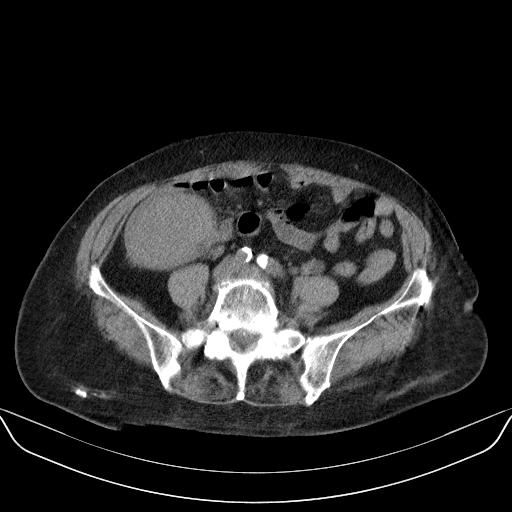

以下是引用yuhongjun在2010-3-12 6:32:00的发言:[br]回肠末端间质瘤,不除外阑尾粘液囊腺瘤,臀部注射性肉芽肿钙化. [br] [br]